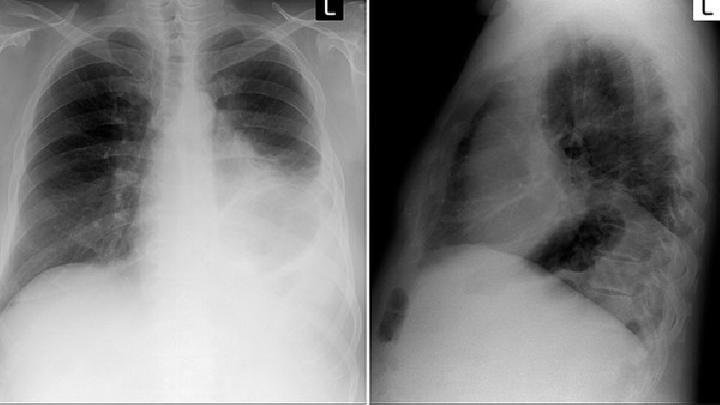

半年前,56岁的魏先生感冒了很久,总是咳嗽,后来还总能咳出带血的痰,加上胸闷不适等症状,他赶紧到医院检查,才发现自己患上了肺鳞状细胞癌。

放射性肺炎是指经放射治疗后,在放射野内的正常肺组织受到损伤而引起的炎症反应。据统计,放射剂量超过4000rad则肺炎明显增多,放射量超过6000rad者,必有放射性肺炎。